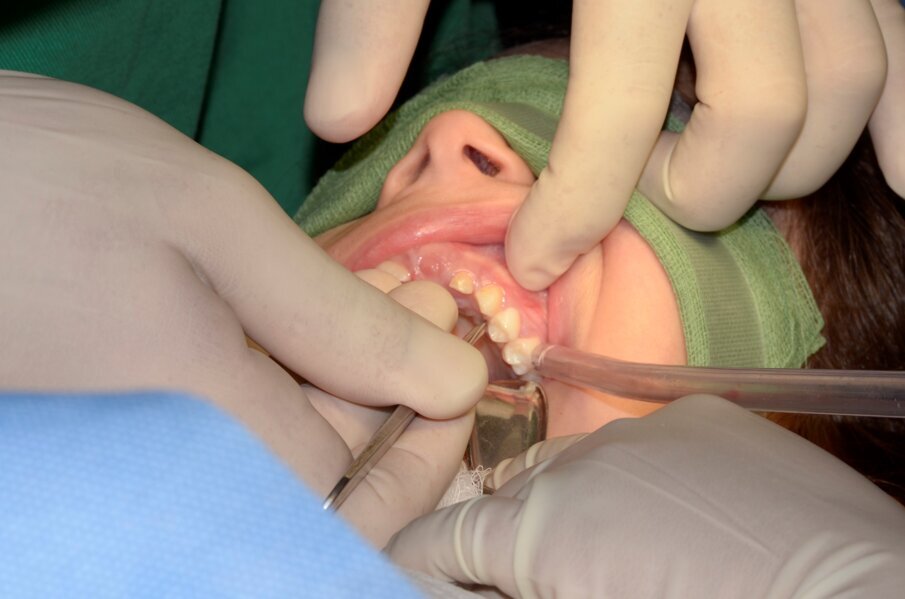

Fig. 5. Palatal intracrevicular incision

- After giving local anaesthesia, a continuous palatal intracrevicular (sulcular) incision was carried out from 54 to 64 (Fig. 5)